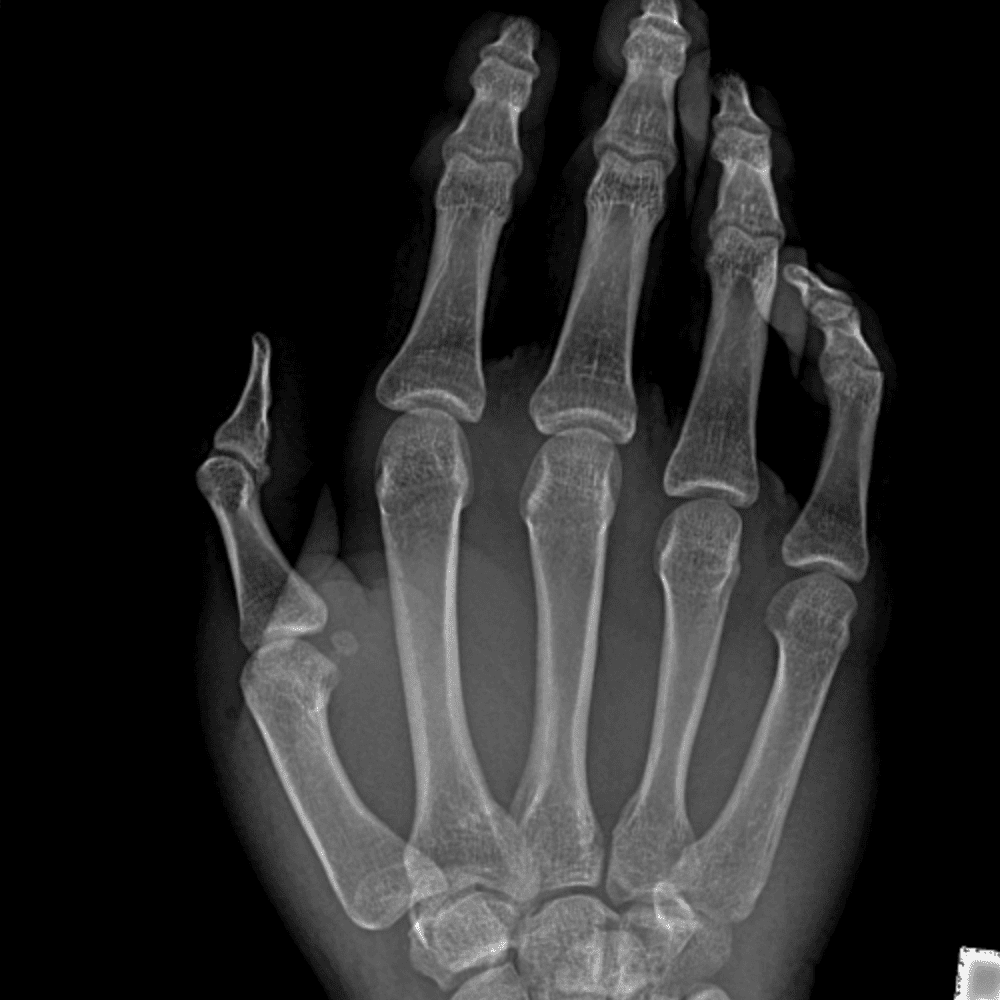

Simulates call by including subtle or difficult cases and some normals.

30 cases